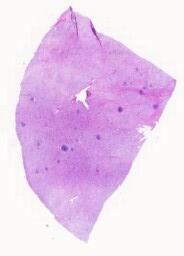

大体所见: 左侧颈部淋巴结:组织数块,3cm×2.8cm×1.5cm,大小不一,质软。

免疫组化: CK-,bcc-6+,Ki67<1%,HMB45+,MelanA-,CDB细胞-,bcc-2++,CD10-,CD45ROT细胞+,CyclinD1+,CD10B细胞+,CD3T细胞+